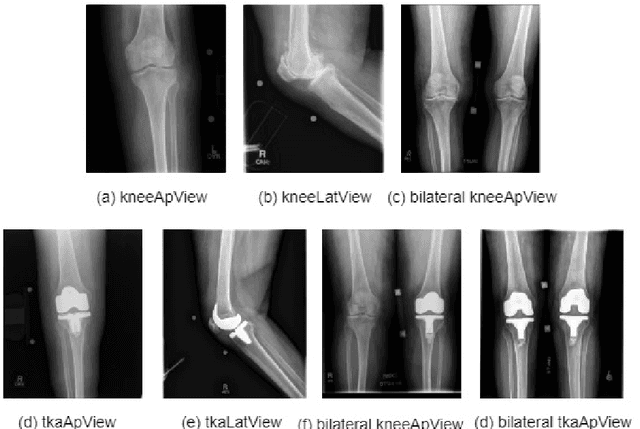

Abstract:Knee pain is undoubtedly the most common musculoskeletal symptom that impairs quality of life, confines mobility and functionality across all ages. Knee pain is clinically evaluated by routine radiographs, where the widespread adoption of radiographic images and their availability at low cost, make them the principle component in the assessment of knee pain and knee pathologies, such as arthritis, trauma, and sport injuries. However, interpretation of the knee radiographs is still highly subjective, and overlapping structures within the radiographs and the large volume of images needing to be analyzed on a daily basis, make interpretation challenging for both naive and experienced practitioners. There is thus a need to implement an artificial intelligence strategy to objectively and automatically interpret knee radiographs, facilitating triage of abnormal radiographs in a timely fashion. The current work proposes an accurate and effective pipeline for autonomous detection, localization, and classification of knee joint area in plain radiographs combining the You Only Look Once (YOLO v3) deep convolutional neural network with a large and fully-annotated knee radiographs dataset. The present work is expected to stimulate more interest from the deep learning computer vision community to this pragmatic and clinical application.